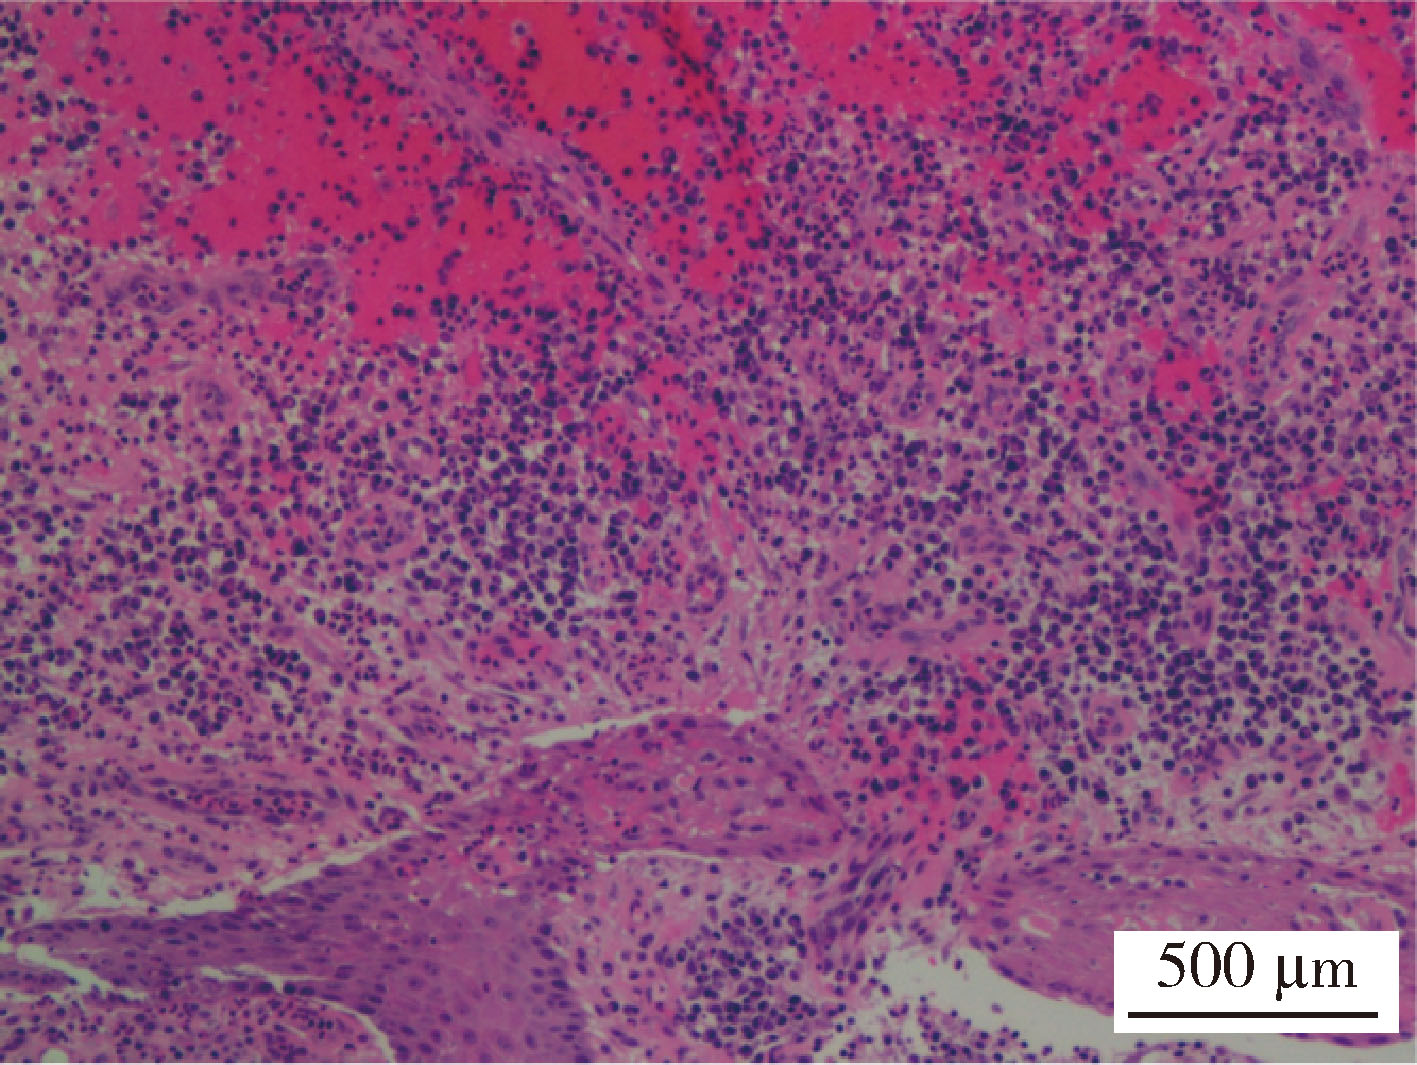

Figure 2

Pathological image of postoperative mandibular mucosal tissue and a small amount of bone tissue (HE ×200) Hematoxylin-eosin (HE) staining showed that the submucosal was infiltrated with lymphocyte, plasmacyte and neutrophils. In addition, fibrous tissue proliferation and granulation tissue formation were found."